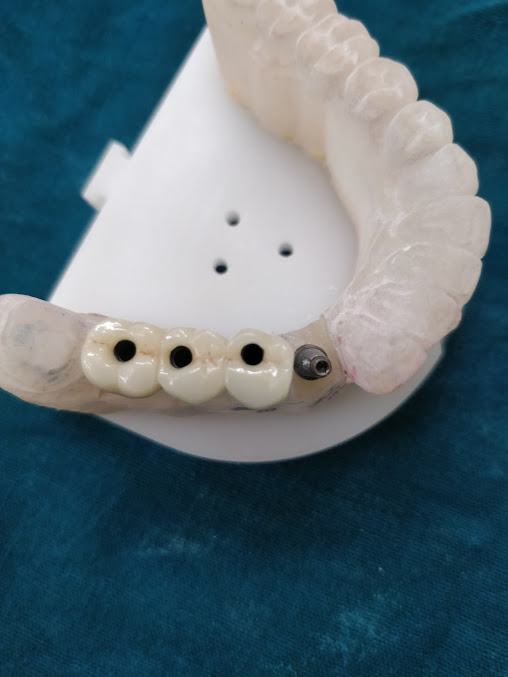

About Dr Joglekars Dental Solutions We are a 23 year old practice at Chinchwad. We take care of our patients for all types of dental problems.We perform --- Family dentistry Orthodontics and clear alignersMicroscope dentistry DIgital smile design Intraoral scanners 3D X ray / CBCT scan Microscope root canal treatment Complete dentures, Implant supported dentures

Dental Implants $349